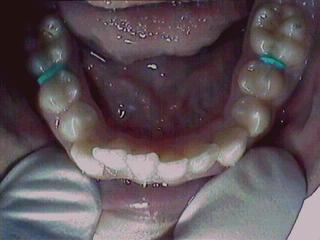

Before Treatment Intra Oral

After Treatment Intra Oral